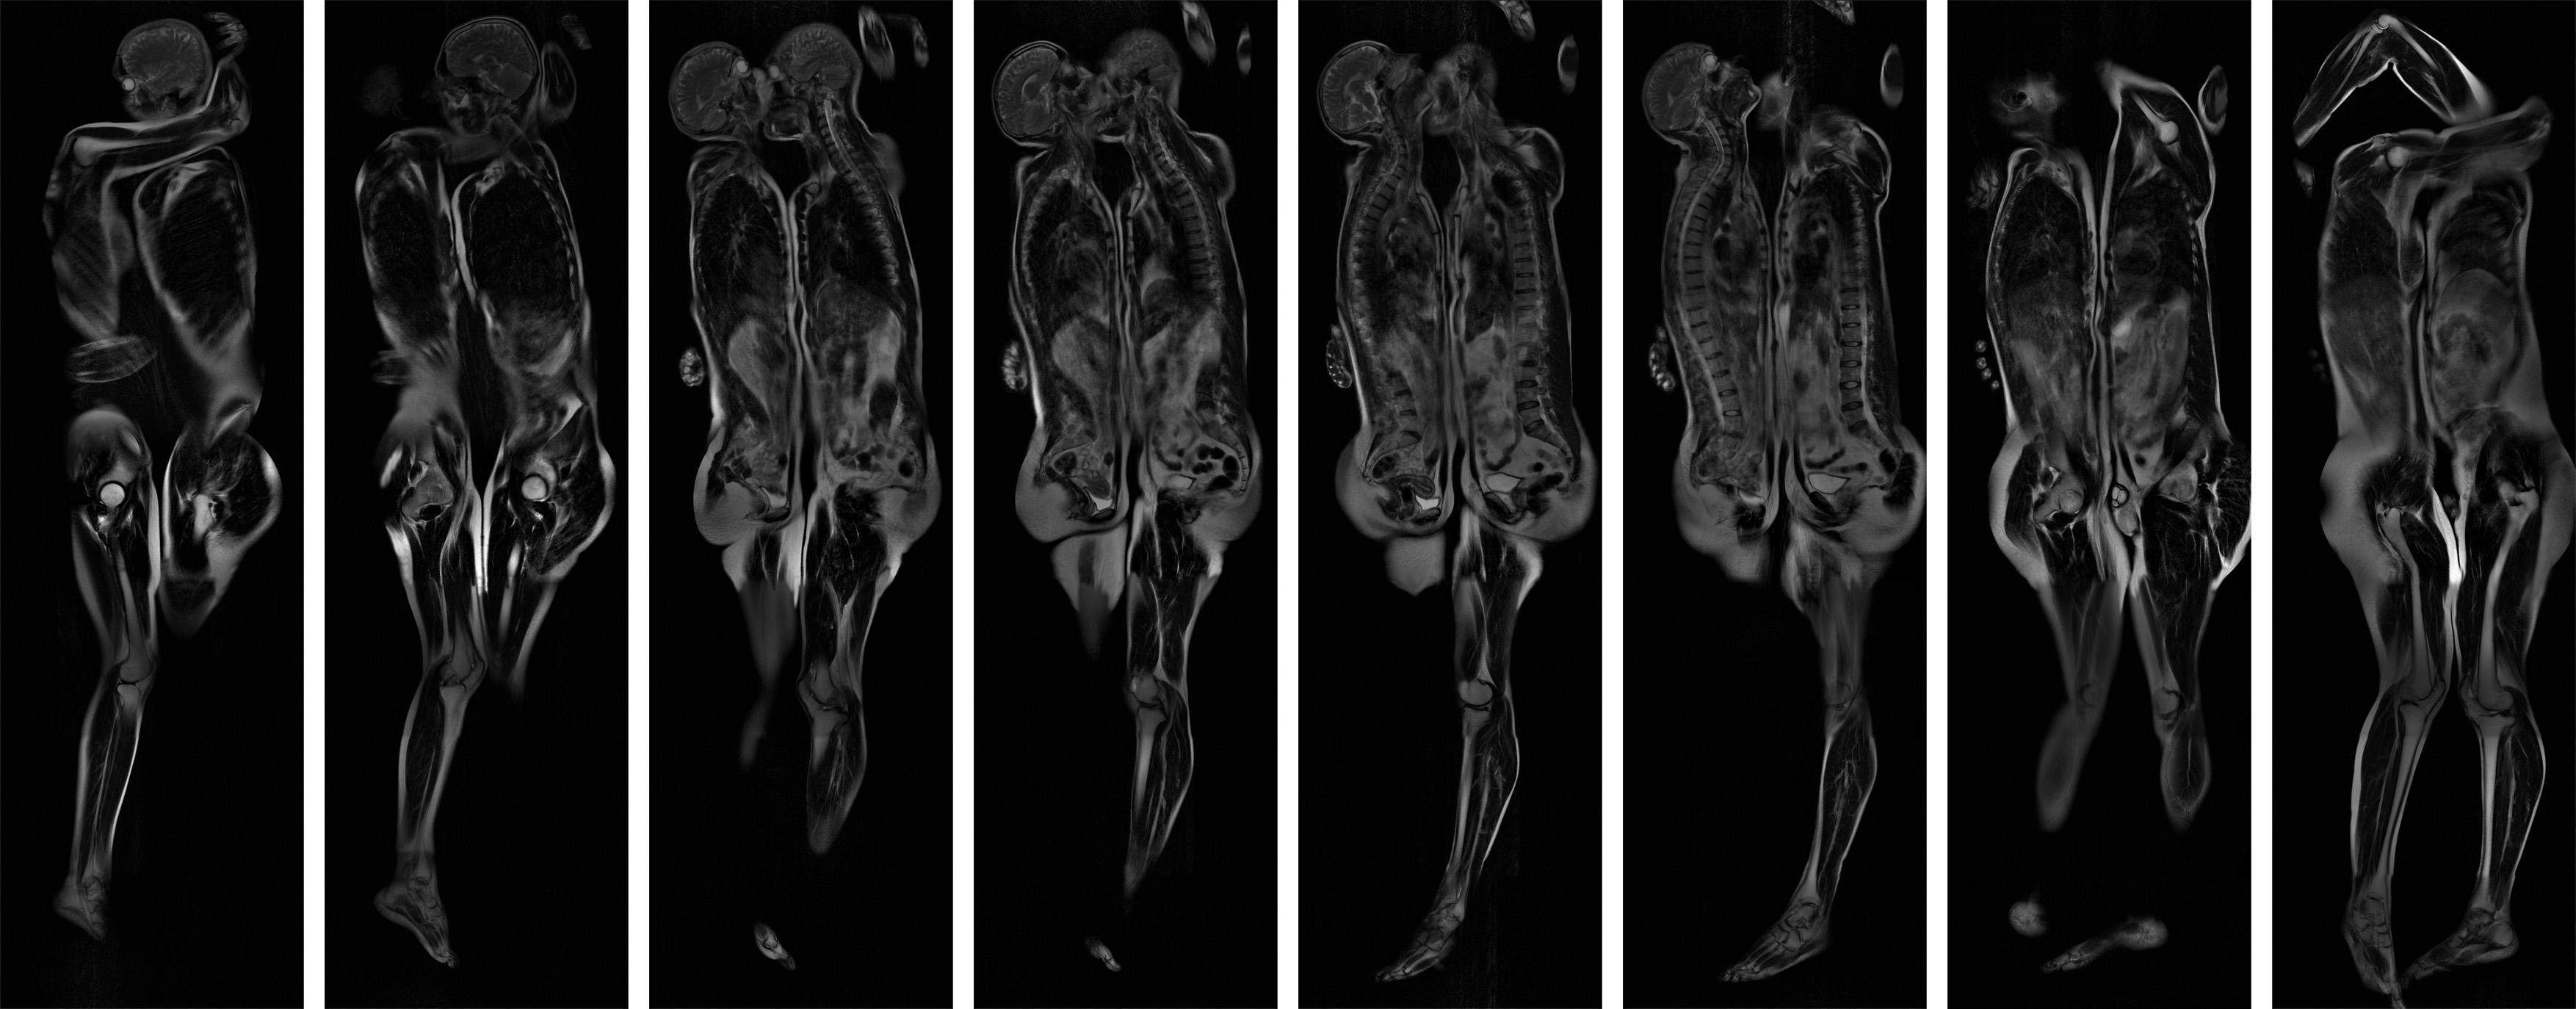

Création art-science réalisée par résonance magnétique et impression en niveaux de gris sur verre feuilleté - Polyptyque de vingt pièces (60 cm × 200 cm).

Nudité du corps sous les vêtements ; Intimité de l'être sous la peau ; Deux d'en d'eux explore l'intérieur de deux personnes pour mettre à l'extérieur leur intérieur ; pour démêler leur intrication mutuelle ; pour attraper leur dynamique commune et laisser battre ces cœurs fragiles.

Deux d'en d'eux est le portrait éclaté d'une étreinte rendant à l'espace ce qu'elle a volé au temps pendant l'infime durée de mesure du signal de désintégration par induction libre émis par les spins nucléaires des atomes d'hydrogène des molécules d'eau composant les organismes vivants. Deux d'en d'eux est un corps à corps vivant en suspension. Les cœurs battent encore et le monde respire encore.